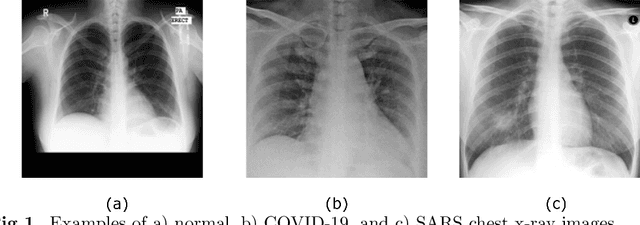

Abstract:Chest X-ray is the first imaging technique that plays an important role in the diagnosis of COVID-19 disease. Due to the high availability of large-scale annotated image datasets, great success has been achieved using convolutional neural networks (CNNs) for image recognition and classification. However, due to the limited availability of annotated medical images, the classification of medical images remains the biggest challenge in medical diagnosis. Thanks to transfer learning, an effective mechanism that can provide a promising solution by transferring knowledge from generic object recognition tasks to domain-specific tasks. In this paper, we validate and adapt our previously developed CNN, called Decompose, Transfer, and Compose (DeTraC), for the classification of COVID-19 chest X-ray images. DeTraC can deal with any irregularities in the image dataset by investigating its class boundaries using a class decomposition mechanism. The experimental results showed the capability of DeTraC in the detection of COVID-19 cases from a comprehensive image dataset collected from several hospitals around the world. High accuracy of 95.12% (with a sensitivity of 97.91%, a specificity of 91.87%, and a precision of 93.36%) was achieved by DeTraC in the detection of COVID-19 X-ray images from normal, and severe acute respiratory syndrome cases.